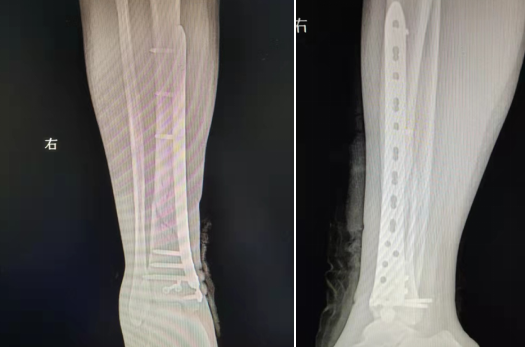

典型病例:女性,56歲,術(shù)前CT提示脛骨中下段骨折,移位明顯。

術(shù)后正側(cè)位片提示骨折達解剖復(fù)位,力線恢復(fù)正常。